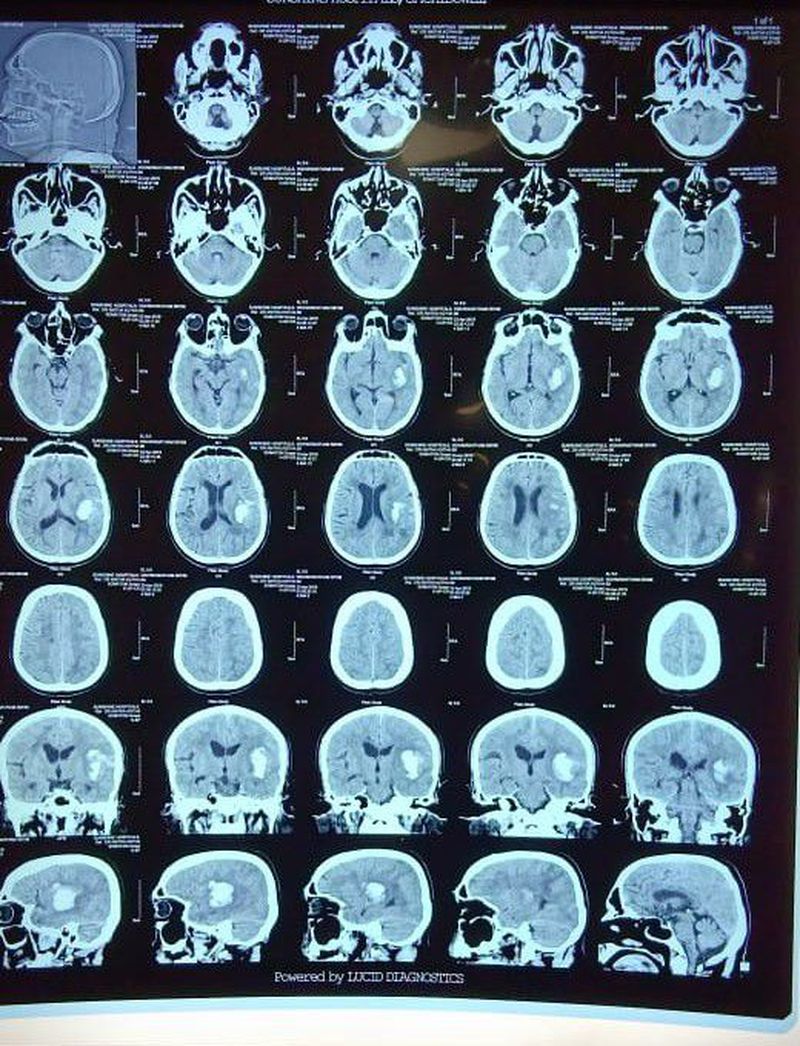

A massive Clot ??

55 Male. DX?

It's an Intraparenchymal hemorrhage